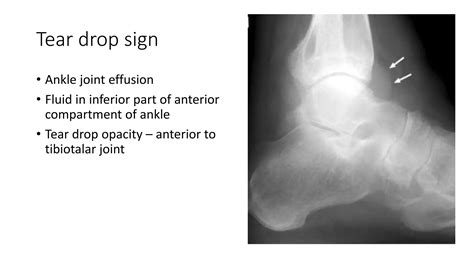

X-rays To rule out fractures or identify signs of chronic osteoarthritis.

MRI Provides detailed visualization of soft tissues, ligaments, and cartilage to identify tears or inflammatory changes.

Ultrasound Highly effective for identifying and quantifying the amount of fluid in the joint space.